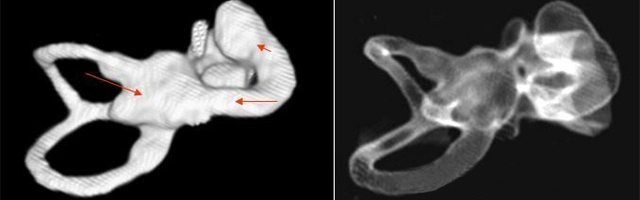

1、診斷

主要依靠顳骨高分辨CT和內(nèi)耳MRI。

雙側(cè)內(nèi)耳畸形:左側(cè)無(wú)內(nèi)耳迷路及內(nèi)耳道機(jī)構(gòu),為米歇爾畸形;右側(cè)空耳蝸及前庭擴(kuò)大,為先天性耳蝸畸形